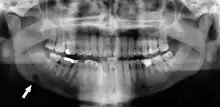

Panoramic radiographs have the capability to demonstrate a portion of the neck and display atheromas (calcifications in the carotid artery) which are an indication of both local and generalized (systemic) atherosclerosis. Atherosclerosis of the coronary arteries leading to myocardial infarction (heart attack), and atherosclerosis of the carotid artery leading to stroke are the number one and number three most common causes of death in the United States.[6]

There is interest to look at panoramic radiographs as a screening tool, however further data is needed with regards if it is able to make a meaningful difference in outcomes.[7]